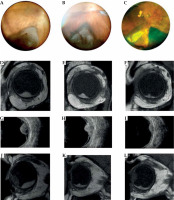

Fig. 1

Case 1. A) Slit lamp photograph reveals the iris portion of the pigmented iridociliary melanoma involving the anterior chamber of the eye at diagnosis. B, C) Slit lamp appearance at 1 and 3 years after ruthenium plaque showing a marked regression of the iris portion of the tumor. A radiation-induced cataract had been removed and an intraocular lens inserted; a posterior synechiae developed as a radiation effect. D-F) Transversal high-frequency ultrasound of the iridociliary melanoma before treatment and at 1 and 3 years after ruthenium plaque. G) Longitudinal high-frequency ultrasound of the iridociliary melanoma before treatment reveals its’ posterior extension into the ciliary body and the rupture of iris-pigmented epithelium. H, I) Regression of the ciliary-body tumor at high-frequency ultrasound, but the anterior chamber angle is involved

Patient number 1 was a 58-year-old male patient with a pigmented iris and ciliary body melanoma on the left eye. On slit lamp physical examination, he presented dilated and tortuous episcleral blood vessels in the upper sector, and a nodular pigmented neo-formation placed between 10 and 1, occupying the iris stroma from the root, with an expansive growth in the anterior chamber to the corneal endothelium, as shown in gonioscopic image. Although the lesion involved the iridocorneal angle, the ocular tone was in the range of normal (15 mmHg).

During ultrabiomicroscopic examination, it appeared as a ciliary body melanoma with iris extension; the hyperreflective iris pigment epithelium was partially eroded by tumor. Internal reflectivity was low. It extended from the pars plana to the intermediate portion of the iris, with infiltration of the iridocorneal angle up to the corneal endothelium. Posteriorly, it displaced the lens. Its’ thickness was measured 5.4 mm, with the largest basal diameter of 13 mm. Based on these findings, a clinical diagnosis of the iris and ciliary body melanoma with anterior chamber invasion was made. The AJCC 8° edition stage was T2bN0M0. The patient underwent IRT with 106Ru CCB plaque (prescribed dose 100 Gy) in 2017. At 1-year post-IRT, the tumor showed partial remission; the pupil was irregular due to the presence of posterior synechiae. After 3 years, an ultrasound documented a remarkable reduction in tumor size, consisting in a flat area of iris pigmentation, and a ciliary body nodule with a thickness of 2.4 mm with increased acoustic reflectivity. The patient underwent cataract surgery; the best corrected visual acuity decreased from 20/25 at baseline to 20/63 at 1-year follow-up, and 20/200 at 3-year follow-up. The patient is still alive, with no evidence of recurrence.